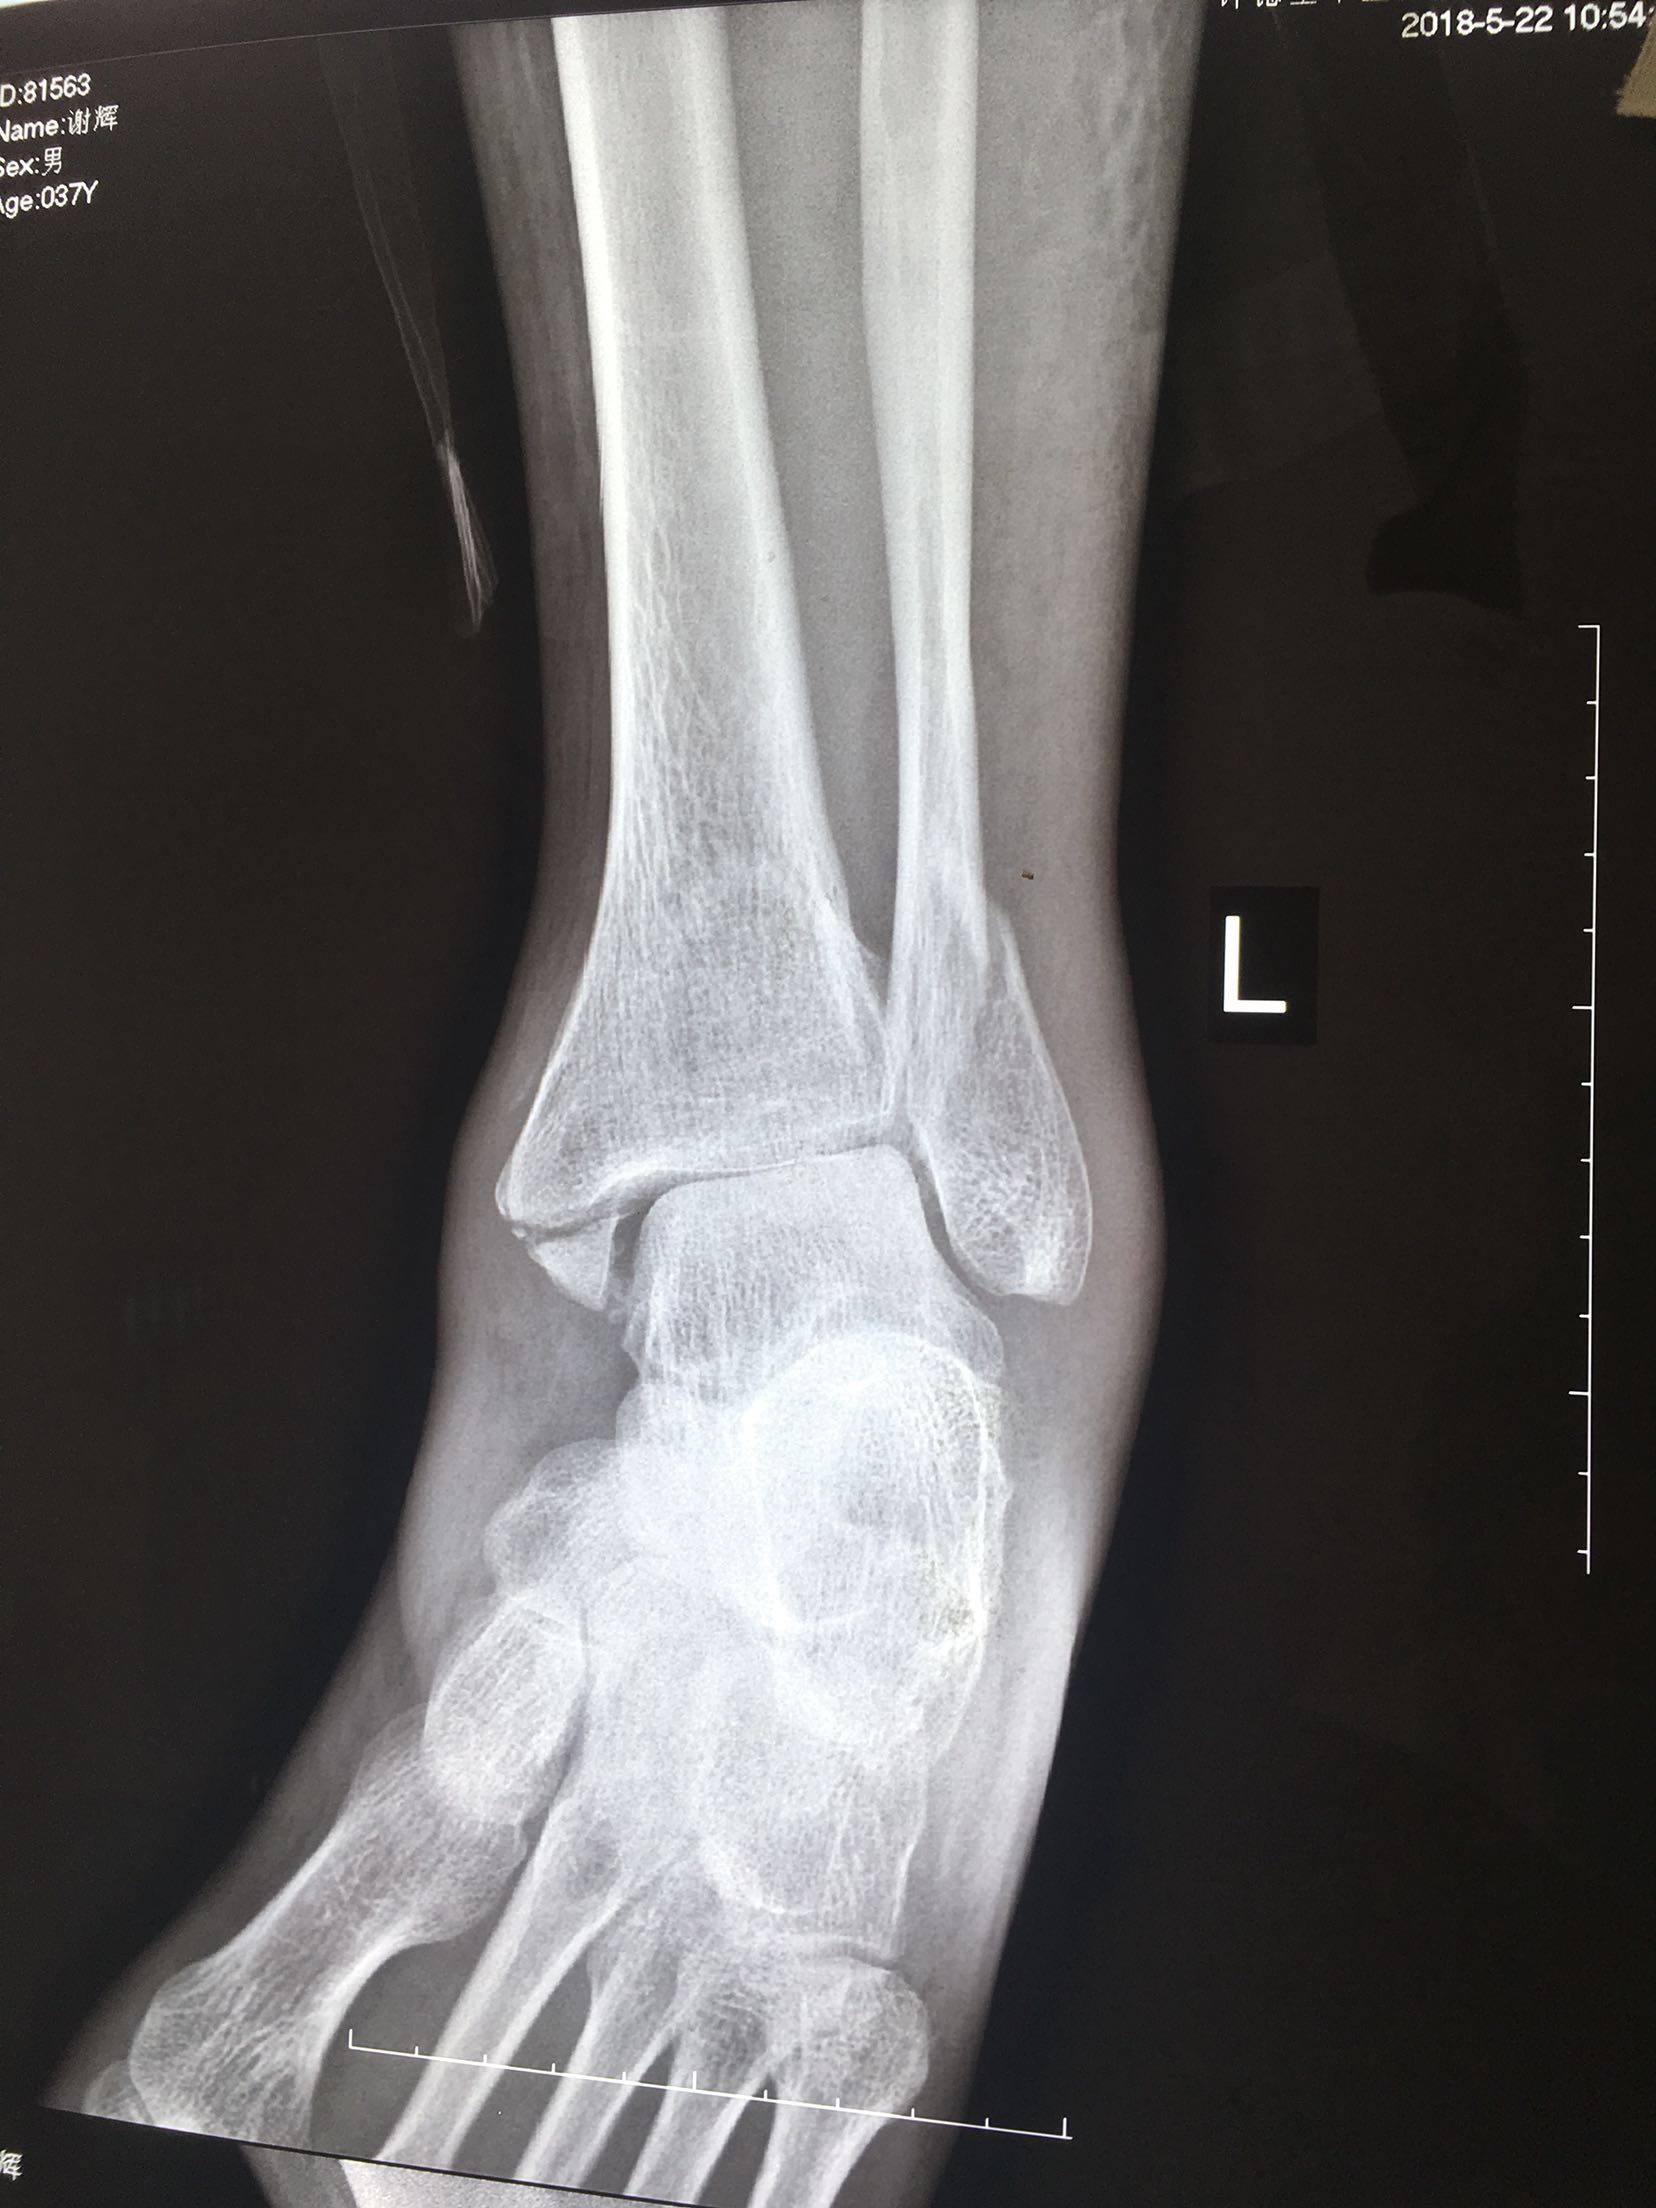

三踝粉碎性骨折(切复内固定)

患者,男,37岁,摔伤后右踝肿痛,畸形,活动受限3小时入院。既往身体健康,无特殊不良嗜好。

右踝部肿胀明显,局部皮色发红,皮温高,畸形,环形压痛,纵叩痛,末梢血运感觉正常,余未见异常。

急诊行跟骨结节牵引,术后一周肿胀消退,在腰麻下行切复内固定术,术后制动抬高,抗炎,消肿等对症处理。